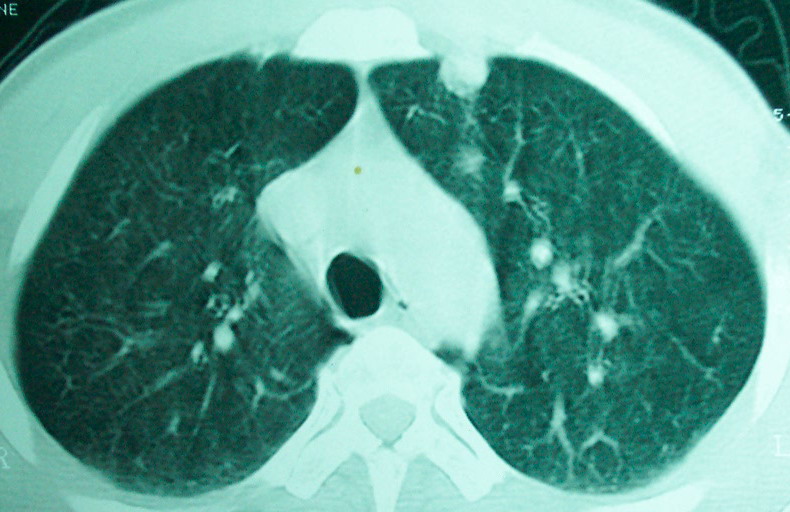

m      37y      发热   咳脓痰月余      ct肺脓肿但住院抗炎治疗后双肺内结节不知该如何解释

治疗后见左肺下野病灶较前缩小但双肺内结节影似无变化请较各位老师该如何下结论    治疗前wbc14.5 治疗后wbc 11.0

血源性肺脓肿,一般由原发感染灶引起脓毒败血症,在肺部形成小脓肿,病变变化快,容易形成肺气囊,脓气胸,主要与转移瘤鉴别,通过临床病史可分

结合临床发热,咳痰考虑为血源性肺脓肿,不过双肺结节又在肺的边缘,还是小心一点,抗炎后复查吧

除了肺内多发结节和左肺下叶的浓疡病灶,还应注意满肺散在的小结节影,还有右上肺前段支气管内膜不光整这些细节,结合病史,肺内多发结节应考虑结核性肉芽!

如果你仔细的同层面对比,你会发现所有的病灶均有比较明显的吸收、缩小。病变的形态,特别是脓肿的形态、壁的厚薄、内壁均有很大的变化,均在往好的方面发展。与临床症状、血像均符合,治疗效果比较显著,就是肺脓肿并双肺的化脓性炎症灶。